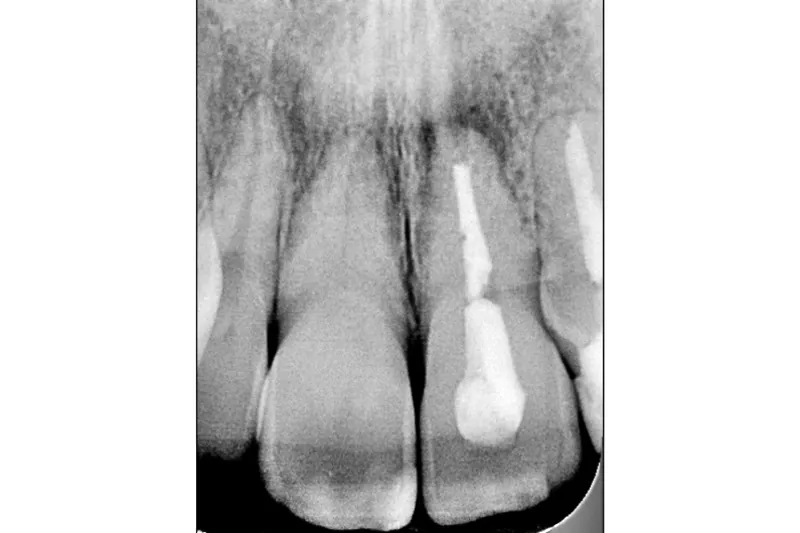

Periapikal kirurgi er en behandlingsmulighed i tilfælde, hvor der efter rodkanalbehandling stadig er tegn på infektion og/eller inflammation i det periapikale område. Der er således typisk tale om tænder med problematisk prognose; men alligevel ser det ifølge en ny dansksvensk undersøgelse ud til, at relativt få af de behandlede tænder mistes i løbet af en periode på 10 år.

Forskere fra Odontologisk Institut (Københavns Universitet) og en række svenske forskningsafdelinger har i et longitudinelt registerstudie fulgt en kohorte på 5.622 tænder, der ifølge det svenske sygesikringssystem (Försäkringskassan) fik foretaget periapikal kirurgi i løbet af 2009, frem til udgangen af 2020.